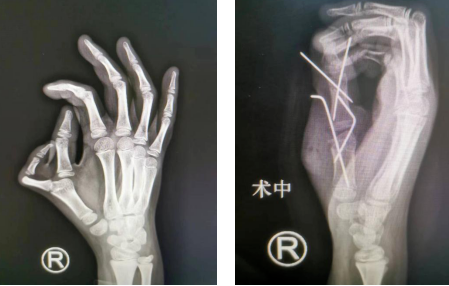

前不久,我院小儿骨科收治1名9岁双侧拇指多指畸形患儿,患儿左手拇指多指畸形II型,右手VII型。李甲主任、李海建、王大伟医生手术团队先为患儿做了“右拇指多指切除截骨矫形内固定肌腱韧带重建带蒂皮瓣修复术”,手术很成功。

术前(左图)术后即刻(右图)

术前组织手术方案讨论,李甲主任考虑,患儿主拇指近节、远节均偏斜,需要截骨矫形。手术操作首先需要切开皮肤、皮下,切除多余骨骼并彻底切除异常形态骨骺,保留侧副韧带、肌腱、部分皮肤组织瓣。